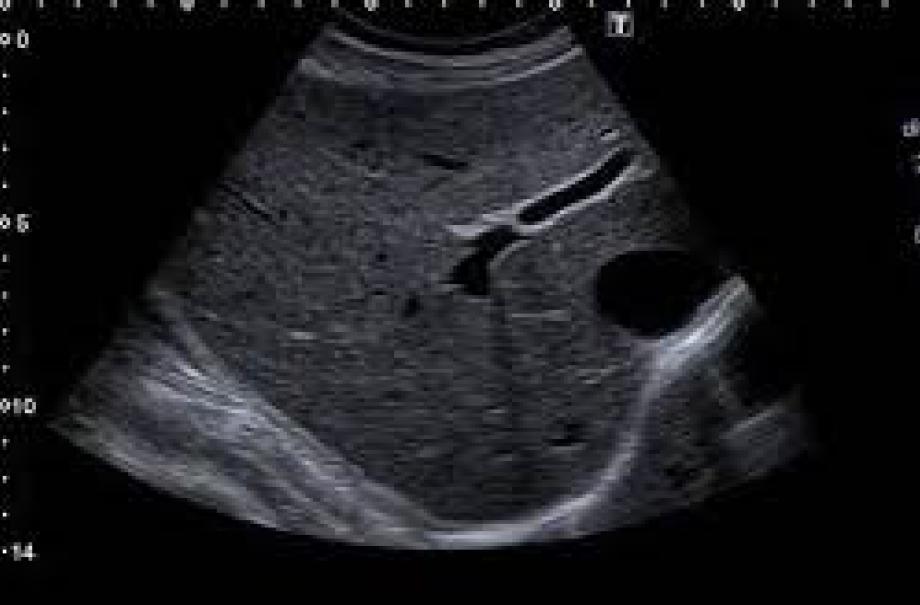

Scanarea abdominală superioară

O investigație detaliată pentru a analiza mărimea, caracterul și forma rinichilor, ficatului, vezicii biliare, splinei, sistemului biliar și pancreasului.